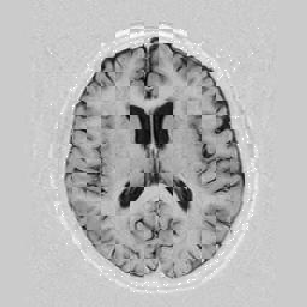

The results are shown for another pair of images in Figure [*].

Figure: Multi-scale NRR. From left to right, top then bottom: before NRR; after 5 iterations of NRR at level 2; after another 5 iterations of NRR at level 1.